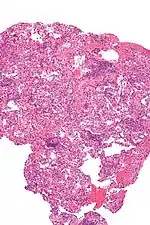

Chronic rejection, meaning repeated bouts of rejection symptoms beyond the first year after the transplant surgery, occurs in approximately 50% of patients.[23] Such chronic rejection presents itself as bronchiolitis obliterans, or less frequently, atherosclerosis.[23]